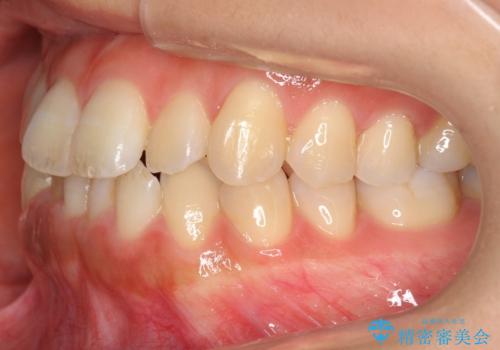

前歯のがたつき インビザラインで 下の奥歯を後ろに下げる

- 上下の前歯のがたつきを主訴に来院。

骨格的に受け口の傾向があり、下の奥歯が前方にに位置しており、下の前歯が特にがたつきが大きい状態でした。

下の奥歯を後ろに下げて下の前歯が前方に出ないように治療しました。

矯正用ミニスクリューを用いて治療しています。